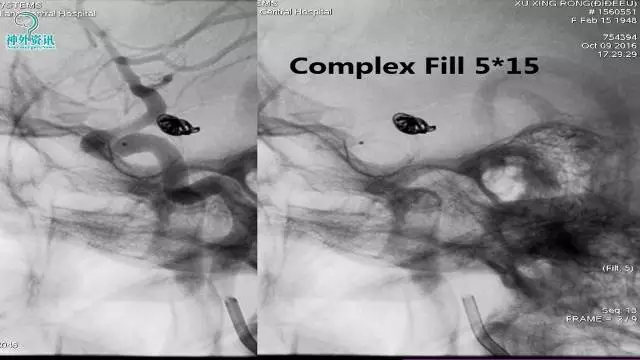

今天为大家分享的是“强生医疗CNV-神经介入专栏”第三十六期,由重庆第三军医大学附属新桥医院神经外科刘俊带来的“Galaxy弹簧圈在不规则动脉瘤中的临床应用”精彩讲课视频及PPT,欢迎观看。文章仅代表作者个人观点,如有不同见解,欢迎同道斧正!